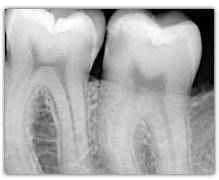

What represent the white, blue, red or black areas which can been seen on the tooth?

According to the pathologies of the tooth (destructured enamel, affected dentine, anfractuous fissure, presence of a crown…), the signal of fluorescence of the dentine will be different (weaker, darker, redder, absent…)

Why is the tooth green on the screen?

The spectrum of the signal of fluorescence (let’s call it "its color") is rather in the green when the dentine is healthy and red/dark when the dentine is infected.

The light must cross the enamel to excite the dentine. Following this excitation, the dentine send back a signal of fluorescence which must cross the enamel to be interpreted. The thicker the enamel is, the weaker the signal of fluorescence is. The intensity of the green light will be weaker and gradually tinted with blue (because of the way through enamel). This is the case for the cusps